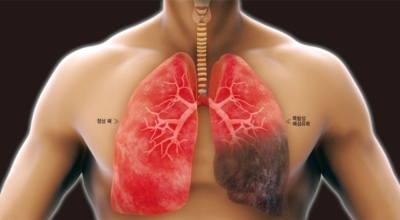

폐렴은 주로 세균이나 바이러스 등 여러가지 원인균이 폐 조직에 감염되어 나타나는 염증성 질환이라고 할 수 있어요. 폐렴의 초기 증상이 감기나 독감과 비슷하므로 주의하셔야 하는 질환 중에 하나이며 한국에서 암 다음으로 3번째 사망률을 보이고 습니다 오늘은 폐렴 증상 폐렴 예방접종에 관하여 알려드려요.

폐렴의 원인은 주로 세균이나 바이러스,곰팡이 감염으로 인해 발생하며 그리고 부식성 화학약품이나 먼지 및 가스를 흡입하던가 음식을 삼키는 기능이 떨어져 있는 사람에게 흡인성 폐렴이 발생하기도 합니다. 폐로 음식물이 들어가면 직접 없애기가 어려우며 음식을 삼키는 기능이 떨어져 있다면 언제든지 감염이 반복될 수 있어 주의해야 합니다.